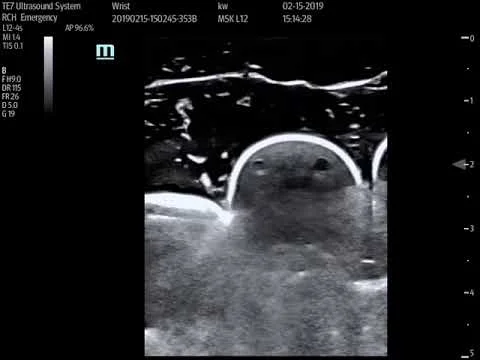

Distal radius fracture

Synovial thickening R wrist